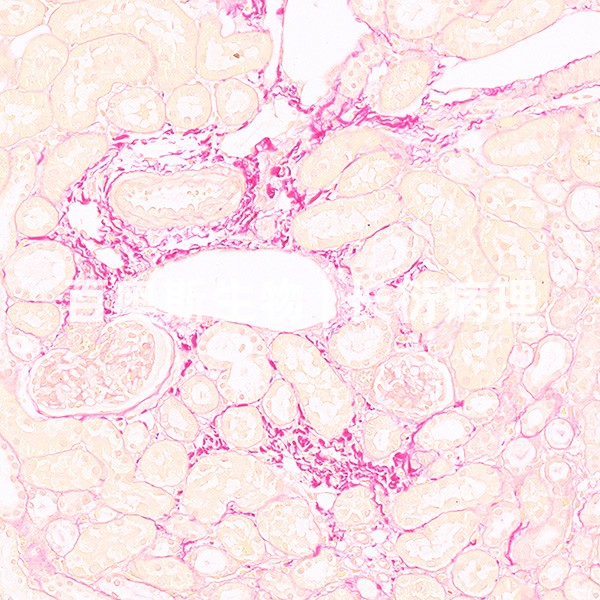

Masson染色